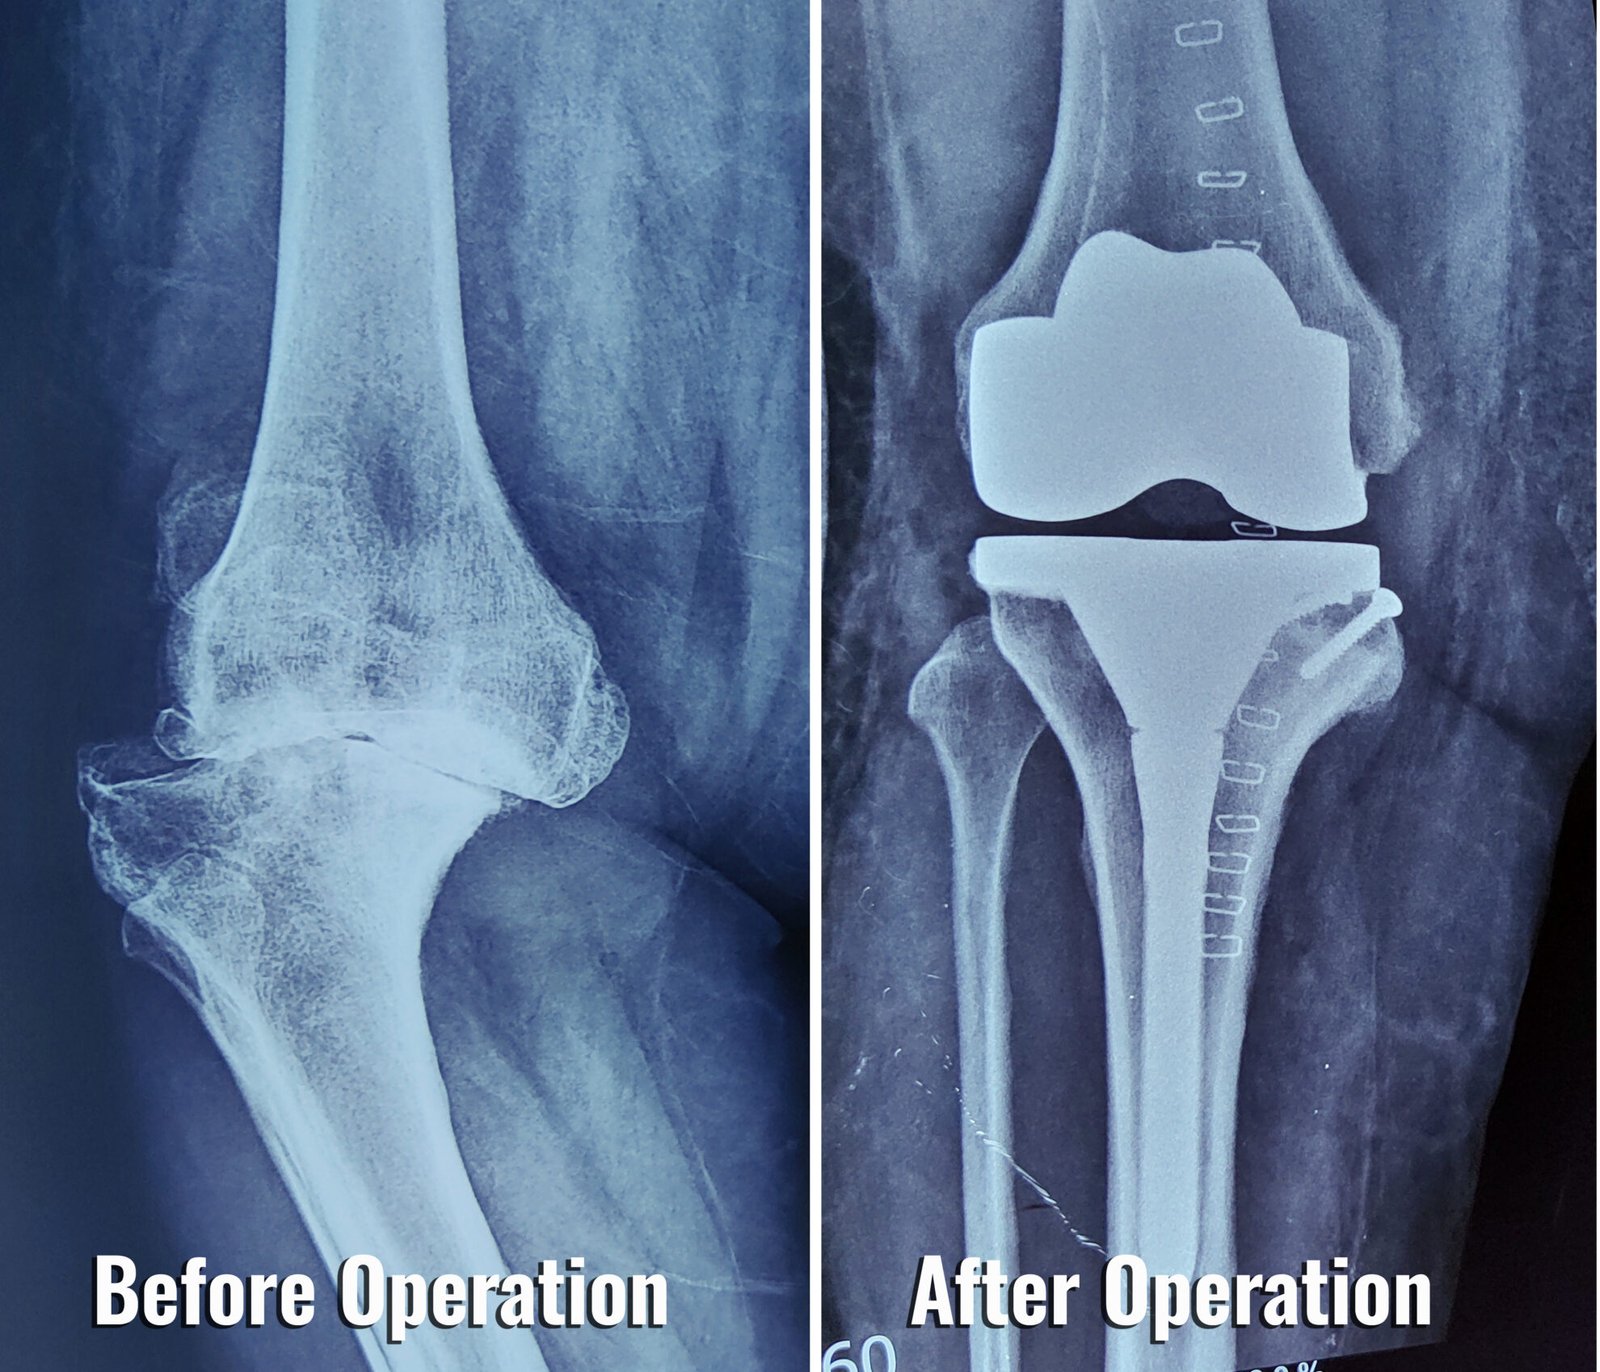

Augmented Reality Knee Replacement . The process begins when surgeons take a preoperative ct scan of the patient’s knee for surgical planning and then use ar glasses during surgery. Nextar knee is a personalized, proprietary, and sustainable augmented reality surgical application for total knee replacement. The augmented reality knee replacement platform—nextar™ tka—received clearance from the fda in 2020. Knee⁺ is an innovative augmented reality solution designed to assist orthopedic surgeons during total knee arthroplasty procedures. In the fall of 2021, mayo clinic performed its first augmented reality knee replacement surgery. Orthopedic surgeons now have a new tool for knee replacement: Medical device innovator, medacta, has today announced the successful completion of the first surgery in the u.s. Augmented reality (ar) technologies aimed to introduce virtual elements into the user’s environment [e.g., superimposition of the.

Medical device innovator, medacta, has today announced the successful completion of the first surgery in the u.s. Orthopedic surgeons now have a new tool for knee replacement: Augmented reality (ar) technologies aimed to introduce virtual elements into the user’s environment [e.g., superimposition of the. The process begins when surgeons take a preoperative ct scan of the patient’s knee for surgical planning and then use ar glasses during surgery. Nextar knee is a personalized, proprietary, and sustainable augmented reality surgical application for total knee replacement. Knee⁺ is an innovative augmented reality solution designed to assist orthopedic surgeons during total knee arthroplasty procedures. The augmented reality knee replacement platform—nextar™ tka—received clearance from the fda in 2020. In the fall of 2021, mayo clinic performed its first augmented reality knee replacement surgery.

Augmented Reality Knee Replacement Knee⁺ is an innovative augmented reality solution designed to assist orthopedic surgeons during total knee arthroplasty procedures. Augmented reality (ar) technologies aimed to introduce virtual elements into the user’s environment [e.g., superimposition of the. Medical device innovator, medacta, has today announced the successful completion of the first surgery in the u.s. Nextar knee is a personalized, proprietary, and sustainable augmented reality surgical application for total knee replacement. Orthopedic surgeons now have a new tool for knee replacement: The process begins when surgeons take a preoperative ct scan of the patient’s knee for surgical planning and then use ar glasses during surgery. Knee⁺ is an innovative augmented reality solution designed to assist orthopedic surgeons during total knee arthroplasty procedures. The augmented reality knee replacement platform—nextar™ tka—received clearance from the fda in 2020. In the fall of 2021, mayo clinic performed its first augmented reality knee replacement surgery.